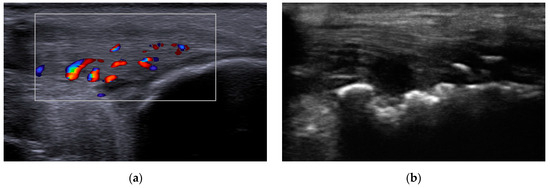

4.3. Musculoskeletal Ultrasound

4.4.2. Measurement of Intima-Media Thickness

| cIMT (mm) | 0.54 ± 0.09 | 0.68 ± 0.17 | 0.0333 |